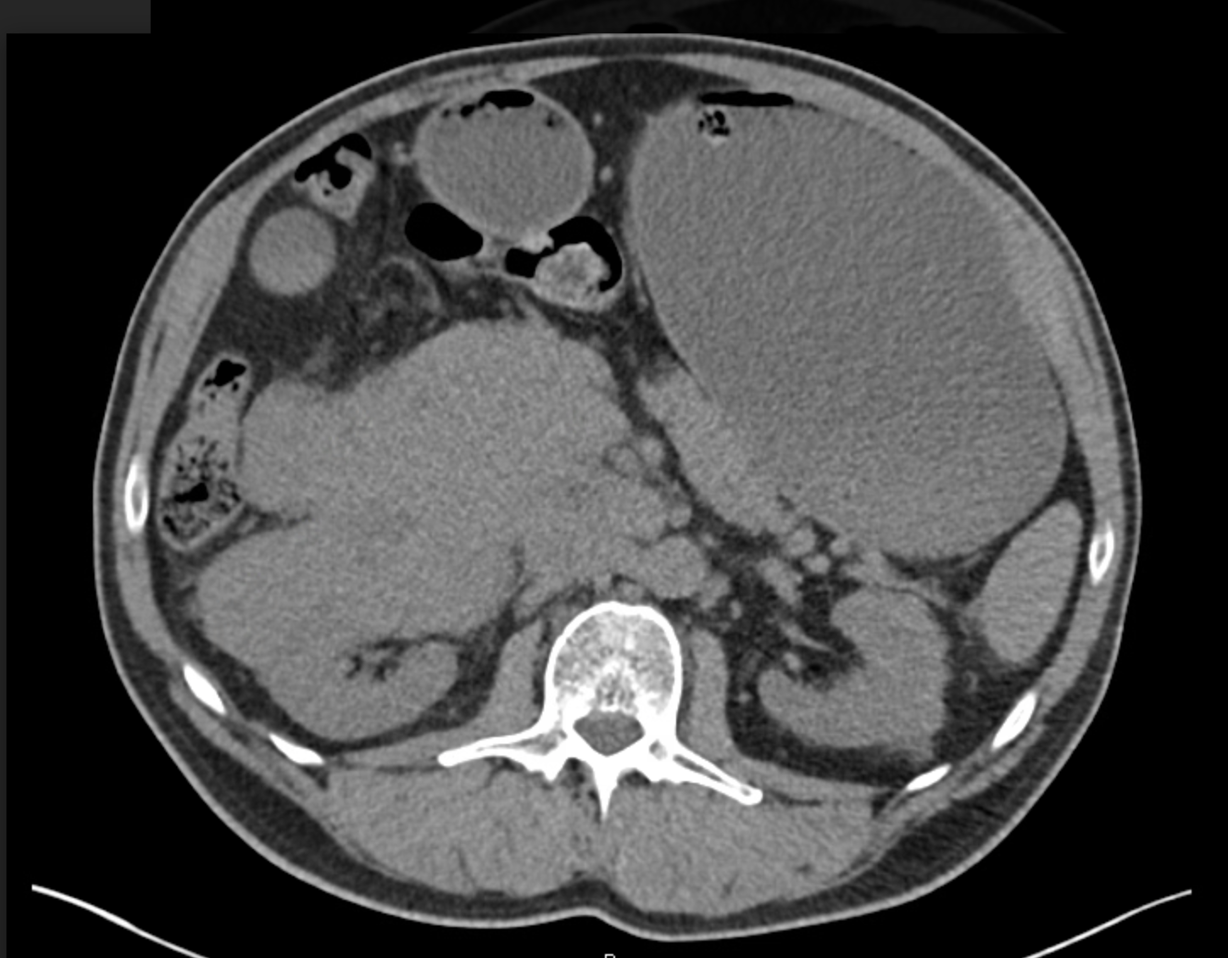

Case Presentation: A 68-year-old male with hypertension and benign prostatic hyperplasia presented with progressive abdominal distension and pain. He denied fever, weight loss, gastrointestinal bleeding, or any history of gastrointestinal diseases. Physical examination revealed a distended, non-tender abdomen with normal bowel sounds.Laboratory tests showed elevated lactate dehydrogenase (LDH) at 750 U/L, hyperuricemia at 9.0 mg/dL, and hypercalcemia at 11.5 mg/dL, suggesting a hematologic malignancy. Abdominal imaging revealed a 10 x 8 cm retroperitoneal soft tissue mass enveloping the renal vessels, inferior vena cava (IVC), and superior mesenteric vein. Initially, renal cell carcinoma was suspected, but biopsy confirmed diffuse large B-cell lymphoma (DLBCL).Shortly after admission, the patient developed nausea, non-bilious vomiting, and worsening abdominal distension, consistent with gastric outlet obstruction (GOO) caused by extrinsic compression from the lymphoma. A nasogastric (NG) tube was placed for decompression, and the patient was started on the R-CHOP chemotherapy regimen. Nutritional support via total parenteral nutrition (TPN) was provided, and over time, his symptoms improved, allowing for the removal of the NG tube.